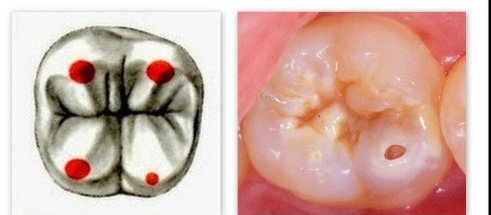

Но просто так за один день кариес ни у кого не образуется. Для этого необходимо время - это месяцы, а чаще годы. Чаще всего кариес развивается в местах, где проще всего задержаться пище - это естественные углубления (фиссуры) и промежутки между зубами.

1 класс - это полости, расположенные в фиссурах и естественных углублениях всех зубов.

Диагностика кариеса не представляет особой сложности даже для рядового человека. Увидеть темноту на зубе или полость - это просто. А вот различить пигментированную фиссуру от кариеса может только врач, как, и найти кариес между зубами. Так рентген и кт как дополнительные методы.

3. Запечатывание фиссур, но это актуально только детям и подросткам.